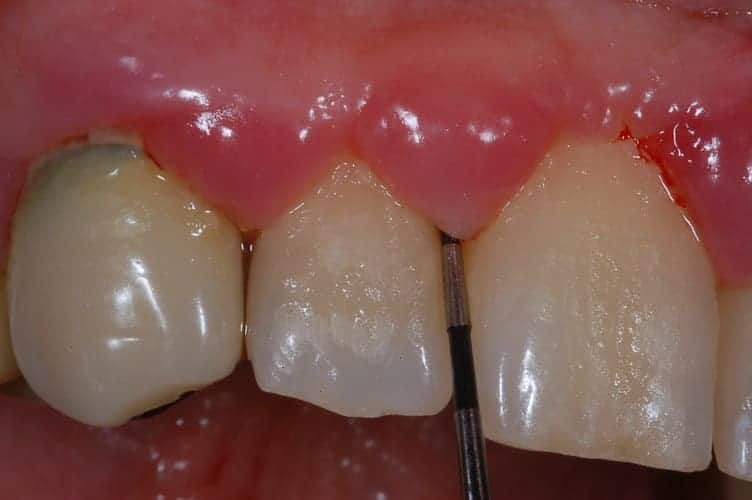

Misurazione tramite sonda della tasca parodontale

Gengive

Tasche gengivali e parodontite o piorrea